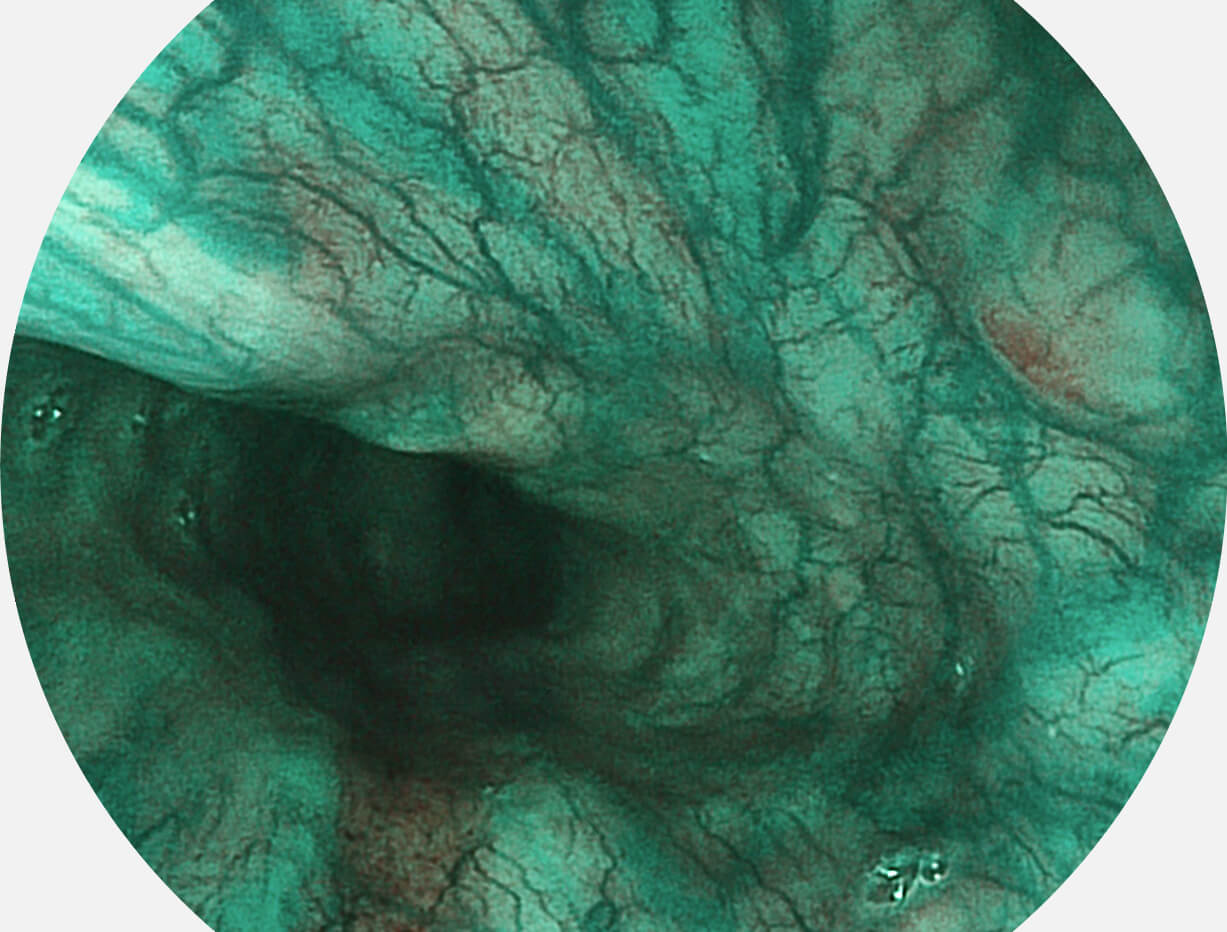

强调浅层黏膜结构的同时,保证照明亮度和提升浅层微血管与中层血管颜色对比度,病变边界更清晰。

VIST图像